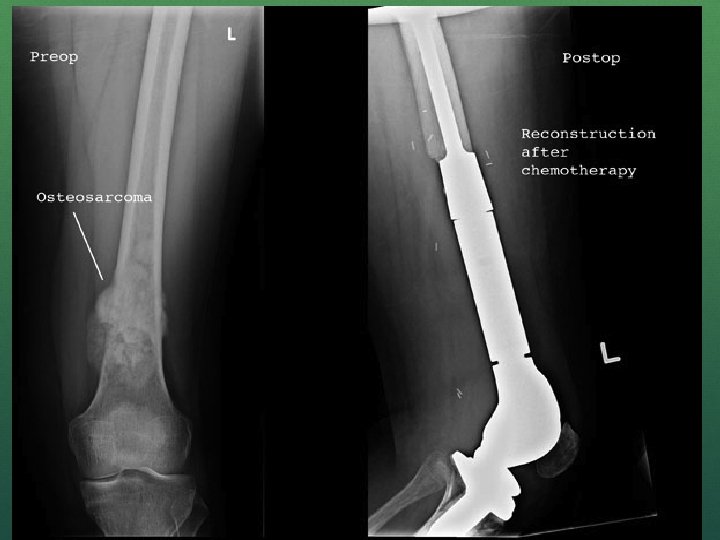

n Classic X-ray findings: 1. 2. 3. 4. Codman's triangle (periosteal elevation) Sunburst pattern/Sunrays appearance Bone destruction Ill-defined margins

Codman’s triangle Sunrays appearance Osteosarcoma

Surgery Disarticulation Amputation Resection with reconstruction/endoprosthesis Limb salvage surgery Resection of metastatic lesion (lobectomy in lung)

Limb salvage surgery Principle is to eradicate the bone tumor, retain integrity of skeletal system and preserve the limb with useful function. After resection, skeletal reconstruction done by bone grafting(auto or allograft) or by endoprosthesis (modular or custom made). Prosthetic reconstruction is more effective As compared to the radical amputation and external prosthetic fitting or limb sparing surgery with bone grafting this treatment is more effective in early mobilization.